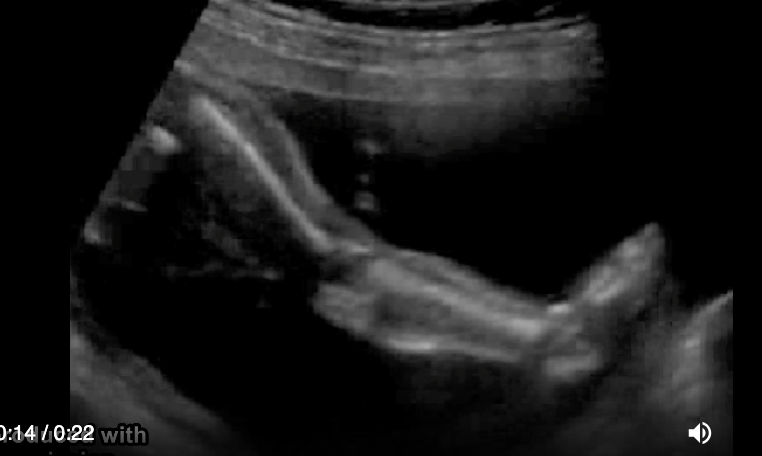

![<p>an abd wall abn that occurs w/abd contents <strong>herniating <em>through abd wall</em> [as in not covered]</strong>layers outside the fetus is</p><p>.</p><p>a) allantoic cyst</p><p>b) omphalocele</p><p>c) gastroschisis</p><p>d) cloacal extrophy</p>](https://knowt-user-attachments.s3.amazonaws.com/fd44542a-011f-4c00-afe9-6ec2cde36bed.png)

an abd wall abn that occurs w/abd contents herniating through abd wall [as in not covered]layers outside the fetus is

.

a) allantoic cyst

b) omphalocele

c) gastroschisis

d) cloacal extrophy